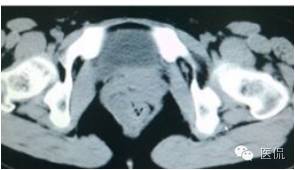

增强延迟期(CT值106HU)

手术是:盆腔占位,病理为:血管肌纤维母细胞瘤。与肛门粘连,于是同时做了肛门的处理。